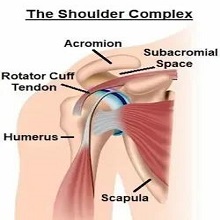

Представља један од најчешћих разлога болне осетљивости рамена. У немедицинским круговима често се описује као „укљештење“ мишића у раменом појасу или „сударање мишића и кости“ у пределу рамена. |